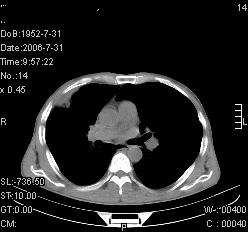

患者,男,54岁,咳嗦,咳痰20天。抗炎治疗2周。现esr76mm/h,目前患者症状明显好转,但发现两次ct片未见明显变化。两次分别做与7.25、7.31。第一次诊断右肺上叶炎症累计胸膜。大家看,从影像上内排除结核吗?

结核的可能性非常大,右上肺病变应该考虑干酪性肺炎。理由:

1.纵隔内多发淋巴结肿大。

2.esr76mm/h。

3.虽经抗炎治疗肺窗病灶有所吸收、减小,但纵隔窗病灶形态、密度、范围无明显变化。如果是单纯的大叶性肺炎,“抗炎治疗2周,目前患者症状明显好转”病灶应该基本消散了,至少也处于吸收消散期,密度变淡、范围变小。同时本病例所示其内的密度不均匀,见多发大小不一空洞样影也不符合大叶性肺炎吸收消散期表现。